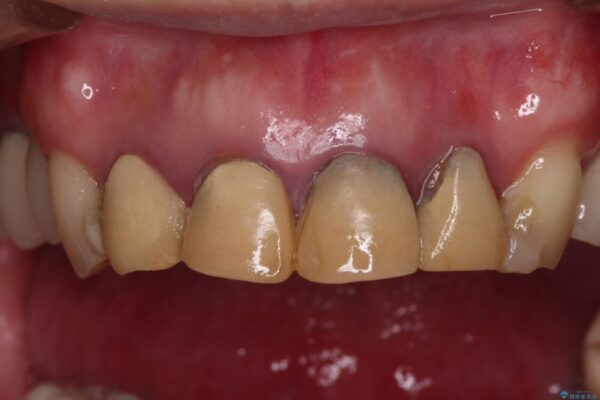

仮歯装着後に放置してしまい、恥ずかしいとのことで来院された患者様です。

仮歯が不適合で歯肉が腫脹していたため、しっかりと調整した新しい仮歯にして腫れを改善した上で、オールセラミッククラウンにて補綴することとしました。

治療前

• 仮歯のまま放置した前歯 オールセラミッククラウンで自然な前歯に 治療前画像